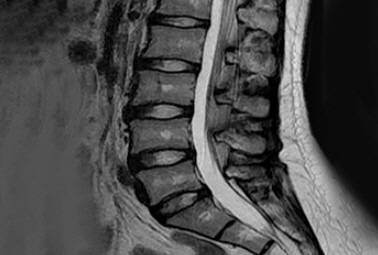

디스크 내장증의 경우 일반 X-RAY나 CT로 발견이 어렵고, MRI 검사를 통해 확인할 수 있어 진단이 늦어지는 경우가 많다.

MRI 검사 시 정상 허리 디스크는 흰색으로 보이지만, 디스크 내장증이 발병한 허리 디스크는 검은색(블랙 디스크)으로 관찰된다.